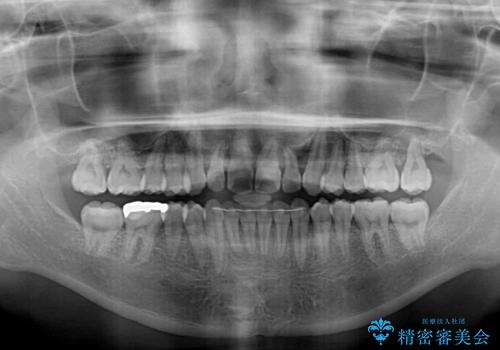

- 上下前歯の叢生を気にして来院された患者様です。

当初はインビザラインにて治療を開始しましたが、自己管理による治療が難しくなり、ワイヤー矯正へ転換して継続しました。

2年ほどインビザライン矯正を続けましたが、終了することができず、ワイヤーへ転換後は1年弱で終えることができました。